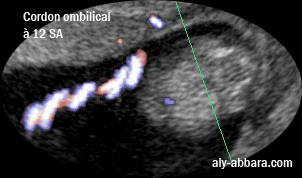

Image échographique montrant l'aspect du cordon ombilical à 12 SA

On constate l'enroulement des deux artères ombilicales autour de la veine ombilicale unique.

Cordon ombilical  : il est composé d'une veine enroulée par deux artères